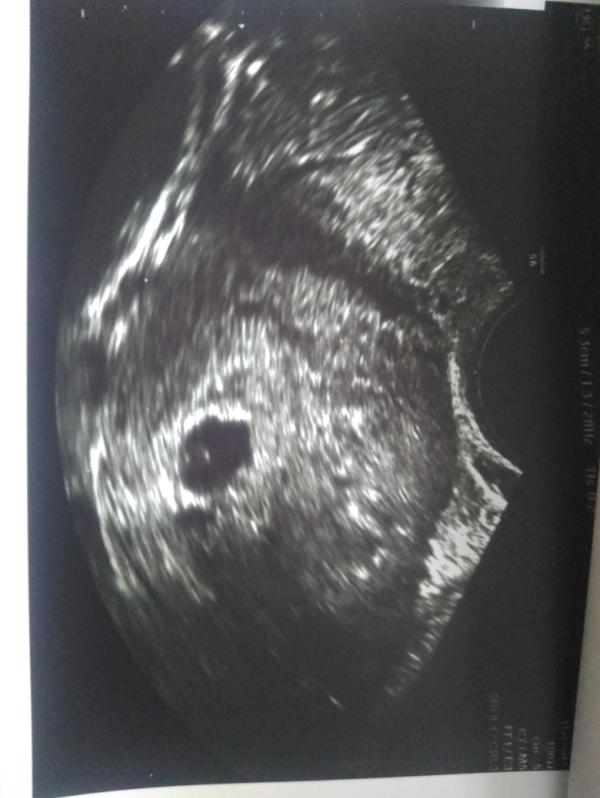

Сходила опять на УЗИ в динамике. Срок 5 недель ставят, длина цервикального канала 40 мм, зев закрыт. Плодное яйцо увидели 9 мм по задней стенке, желточный мешок 4 мм. А бусинку пока не увидели, через две недели опять узи.